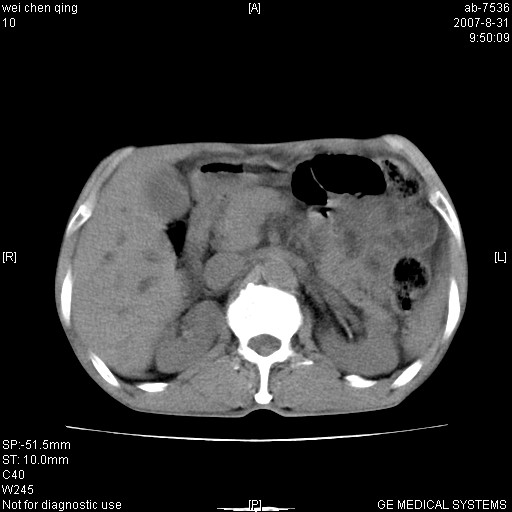

以下是引用zyyzzy在2007-8-31 14:34:00的发言:[br]该病人肝内胆管扩张,胆囊及胆总管未见明显扩张。在倒数第9层图像上可看到左右肝管结合部(肝总管)有软组织影,此处应薄层扫描。考虑肝总管占位(ca)、腹水。[br]